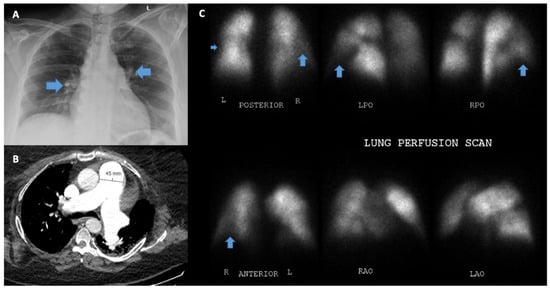

5.8. Ventilation/Perfusion Scanning (V/Q)

| VQ scan [19,20] | 90–100% | 94–100% | Allows us to distinguish CTEPH from other forms of PH, negative test helpful for ruling out CTEPH. | Low utility in diagnosing causes of PH other than thromboembolic disease. |